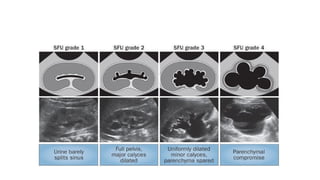

USG

•Widely used as it is non invasive and helps in identification of wide

variety of conditions

•Helps to establish dilatation of PCS

•Can visualise renal / upper ureteric calculi

•Can visualise any gross structural abnormalities

•Mainstay in prenatal imaging, hence useful for diagnosis of Antenatal

Hydronephrosis

Antenatal Hydronephrosis

•Diagnosed during antenatal usg

•Antero posterior diameter of

renal pelvis is measured